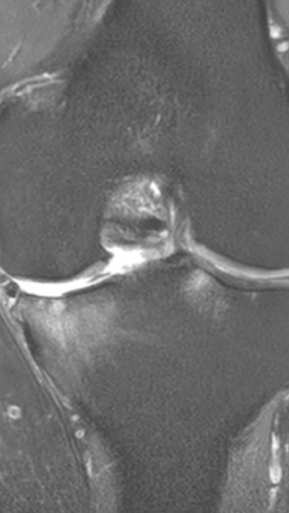

Рецидивирующий синовит коленного сустава

Излечение за 1 процедуру ФДТ РЕВИКСАН

Параметры изменяются в зависимости от процедуры